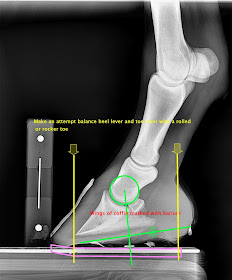

Basically the coffin bone follows closely a proportional development. Once you can identify the tip of p3 and the wings you can then use a golden ratio caliper to find a point that is very close to the mechanical center of rotation of the coffin joint. It has long since been known that managing the forces around the coffin joint are very important and identifying this point on the foot surface can be very consistent. It correlates well with other reported mapping protocols. It commonly lines up with the trimmed bars and widest part of the white line.

Wings can be located very close to the angle of the sole. It is more accurately place at the stratum internum where the bar turns in at the heel. Then carry a line towards the toe very close to parallel to the central sulcus. Where this point crosses the white line will also be very close to the tip of the coffin bone. I confirm this with measuring a thumbs width in front of the apex of the frog. Using the golden means caliper place the short side at the heels and long side at tip of coffin bone. The center point of the caliper will be very close to the center of rotation of the coffin joint. This point will often line up very close to the insertion of the deep flexor tendon as well. A line dropped perpendicular to the wings of the coffin bone and centered on the center of rotation will cross this point on the ground surface of the hoof.

Note the thumb tack and its alignment to the center of rotation of the coffin joint. Also note the barium marking the point located on the heels that corresponds to the wings. In sound young horses with no lameness or pathology I would strive to balance the leverages around this point. Often times a rockered rolled toe is all that is needed. Many coffin bones and hooves have such long toe levers it is impossible to provide even toe and heel levers. One cannot leave excessive heel length as it is a hazard and can act a lever that could lead to a crushing of the horn in the heel. In these case I recommend placing the toe lever as far back as the tip of the coffin bone and adding modifications to the ground surface that improve ground interaction. A combined rolled toe with concaved inner rim and a fullered heel branch will encourage the toe to sink and the heel to float. This will aid in prevention of heavy tendon load and hyperextension of the coffin joint.